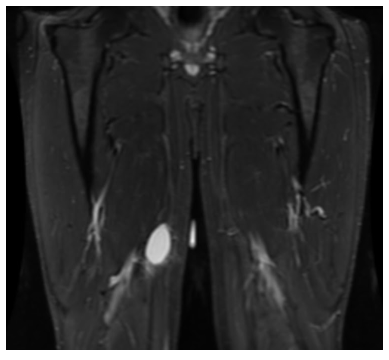

Round Cell Liposarcoma is a malignant, or cancerous, soft-tissue sarcoma that most commonly occurs in the deep tissues of the thigh, or other extremities. It is fairly aggressive and has a greater potential for metastasis.